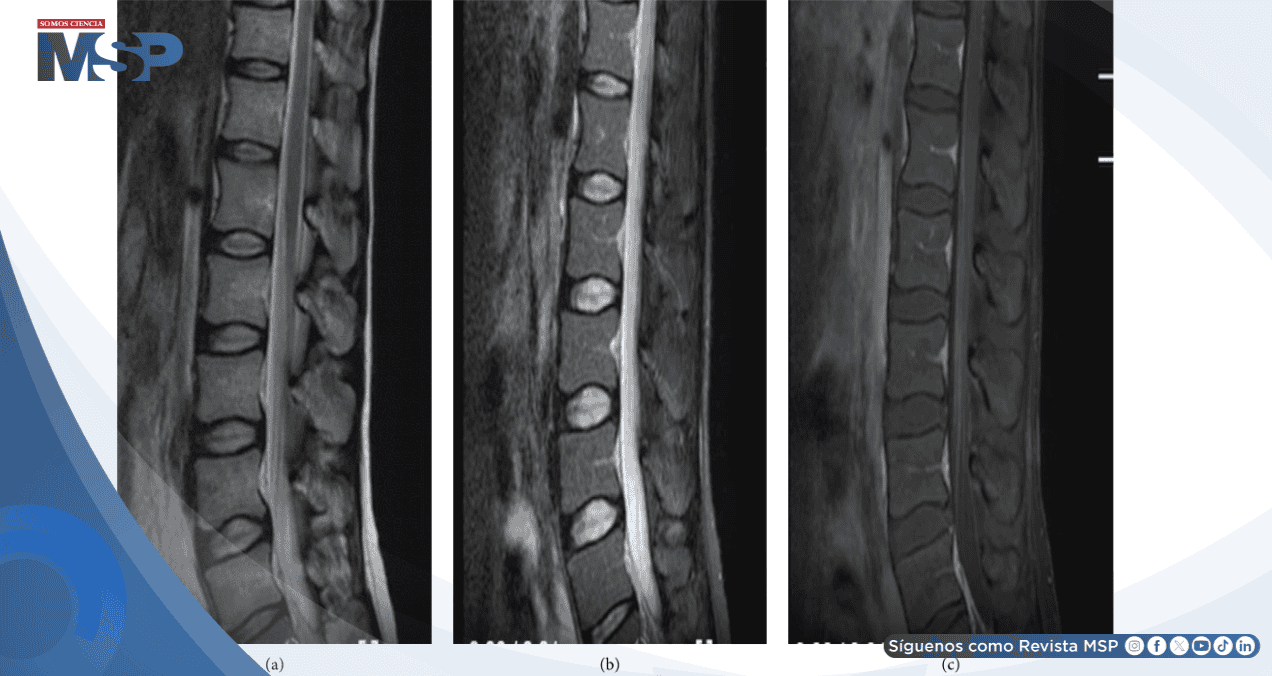

La resonancia magnética espinal fue determinante para el diagnóstico. Las imágenes demostraron hiperintensidad extensa en secuencias T2 y STIR a nivel lumbar, con realce tras la administración de gadolinio.

Las lesiones comprometían más del 50% del diámetro transversal de la médula espinal, criterio diagnóstico de mielitis transversa aguda. Esta presentación radiológica, combinada con el contexto clínico, permitió establecer el diagnóstico definitivo.